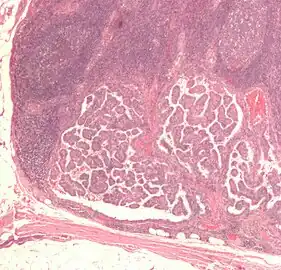

| Micrograph of a papillary thyroid carcinoma demonstrating diagnostic features (nuclear clearing and overlapping nuclei). | |